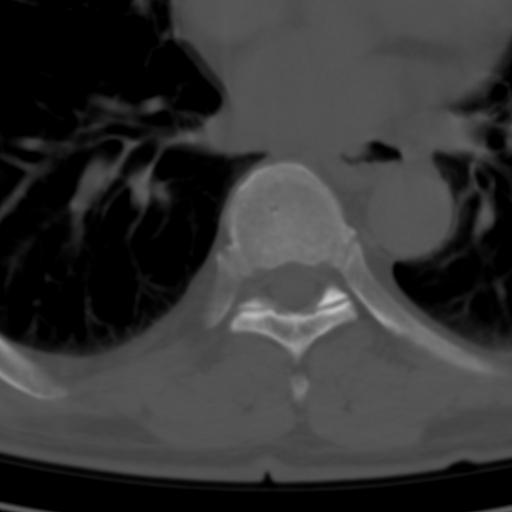

标题: CT25189:胸椎ct,请会诊!

既往食管癌,现行ct检查!

中上段食道癌,椎体轻度退变。

支持中上段食道癌,椎体轻度退变,必要时做ect。